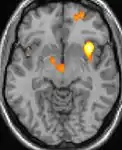

|  |  |  |

| La tomographie par émission de positons (TEP) montre les zones du cerveau étant activées durant la douleur | ||

| La morphométrie voxel par voxel (VBM) montre les différences structurelles des zones du cerveau | ||

Les images par tomographie à émission de positron indiquent les régions du cerveau qui sont activées lors de la douleur, par rapport aux périodes sans douleur. Elles montrent les régions du cerveau qui sont toujours actives durant la douleur en jaune/orange (appelé "matrice-douleur"). La zone au centre (dans les trois vues) est spécifiquement activée uniquement pendant la crise. Les photos sur la ligne du bas (effectuées par VBM) montrent les différences structurelles entre les patients souffrant d'AVF et des personnes saines : seulement une partie de l'hypothalamus est différente[50],[51].